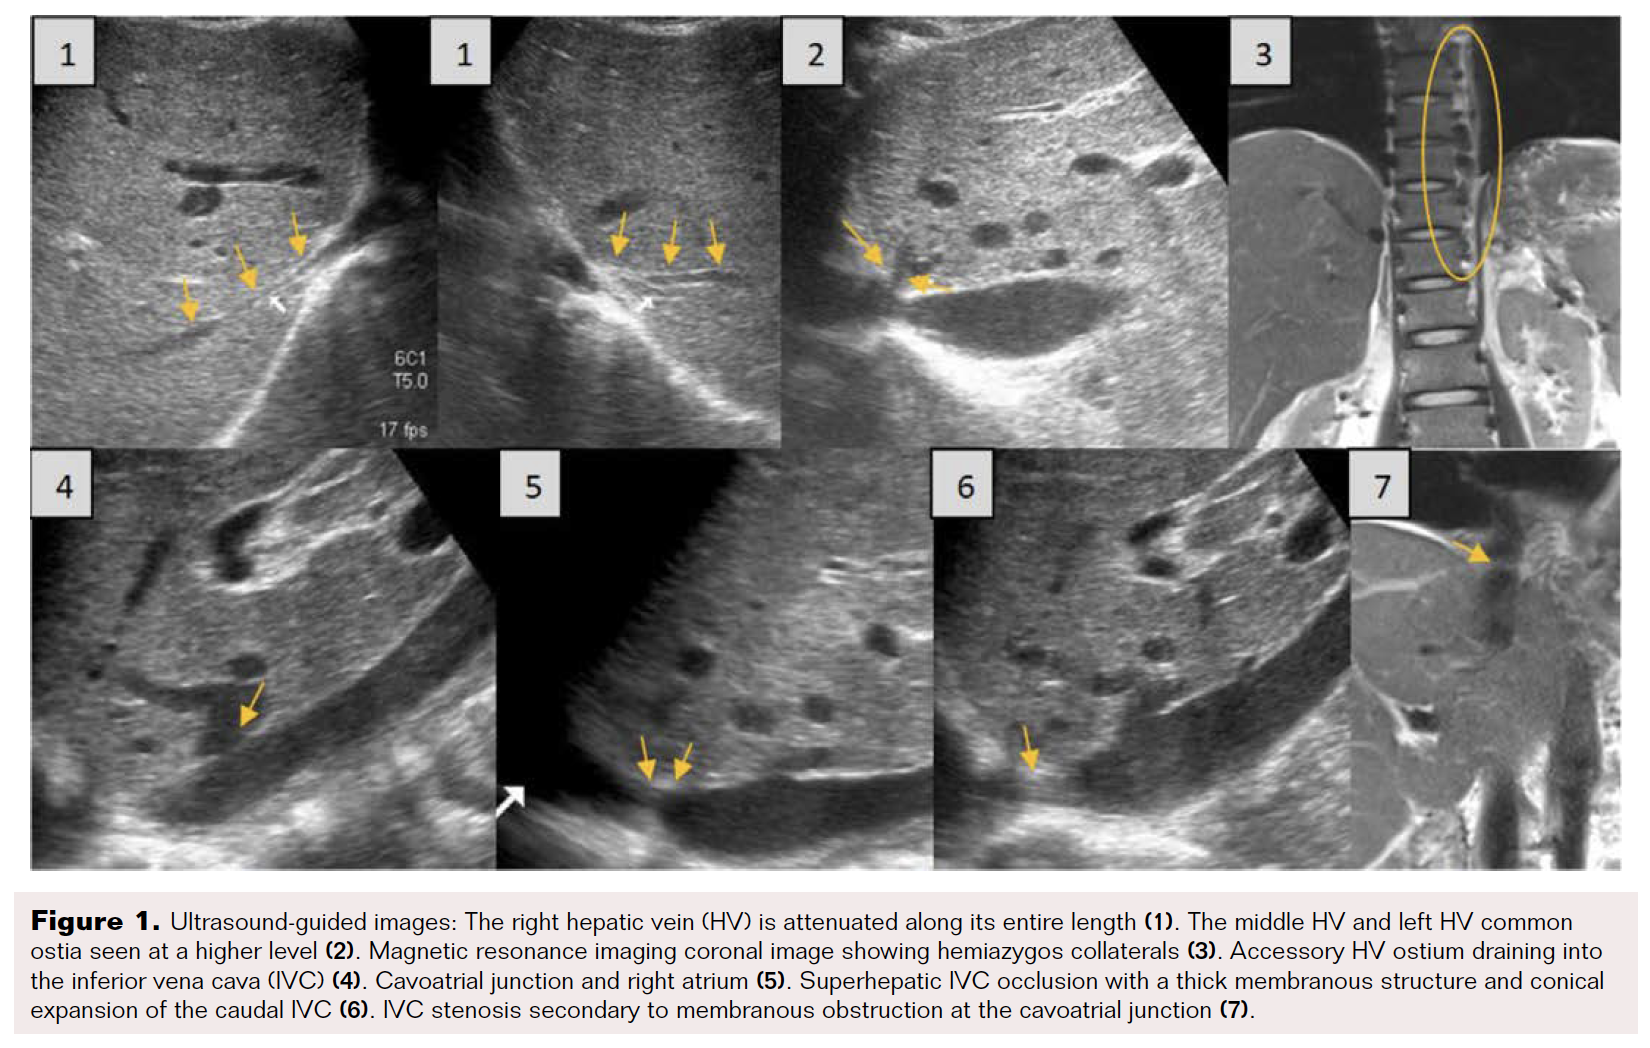

A 29-year-old man presented with intermittent pedal edema and shortness of breath for 2 weeks duration. He also had a history of melena and hematemesis in the past 4 years. On examination, he had enlarged superficial veins on the anterior abdominal wall, hepatosplenomegaly, and bilateral pedal edema. Ultrasound (US) showed splenomegaly, heterogeneous echotexture of the liver, and minimal ascites. On Doppler evaluation, a short-segment (< 5 mm) occlusion of the suprahepatic inferior vena cava (IVC) was noted, with secondary conical dilation of the caudal IVC, resembling the appearance of a minaret.3 The right hepatic vein (HV) was significantly attenuated and irreparable. Middle and left HVs were communicating with long-segment occlusion near the ostia (Figure 1), and intrahepatic collateral veins were seen. Based on the clinical and imaging findings, a diagnosis of Budd-Chiari Syndrome was made.

The Glidewire was exchanged for a 0.035" Amplatz exchange-length wire. Serial balloon angioplasty was performed using 8 mm, 12 mm, and 14 mm diameter balloons. Recanalization of the suprahepatic IVC occlusion was observed on US (Figure 3).